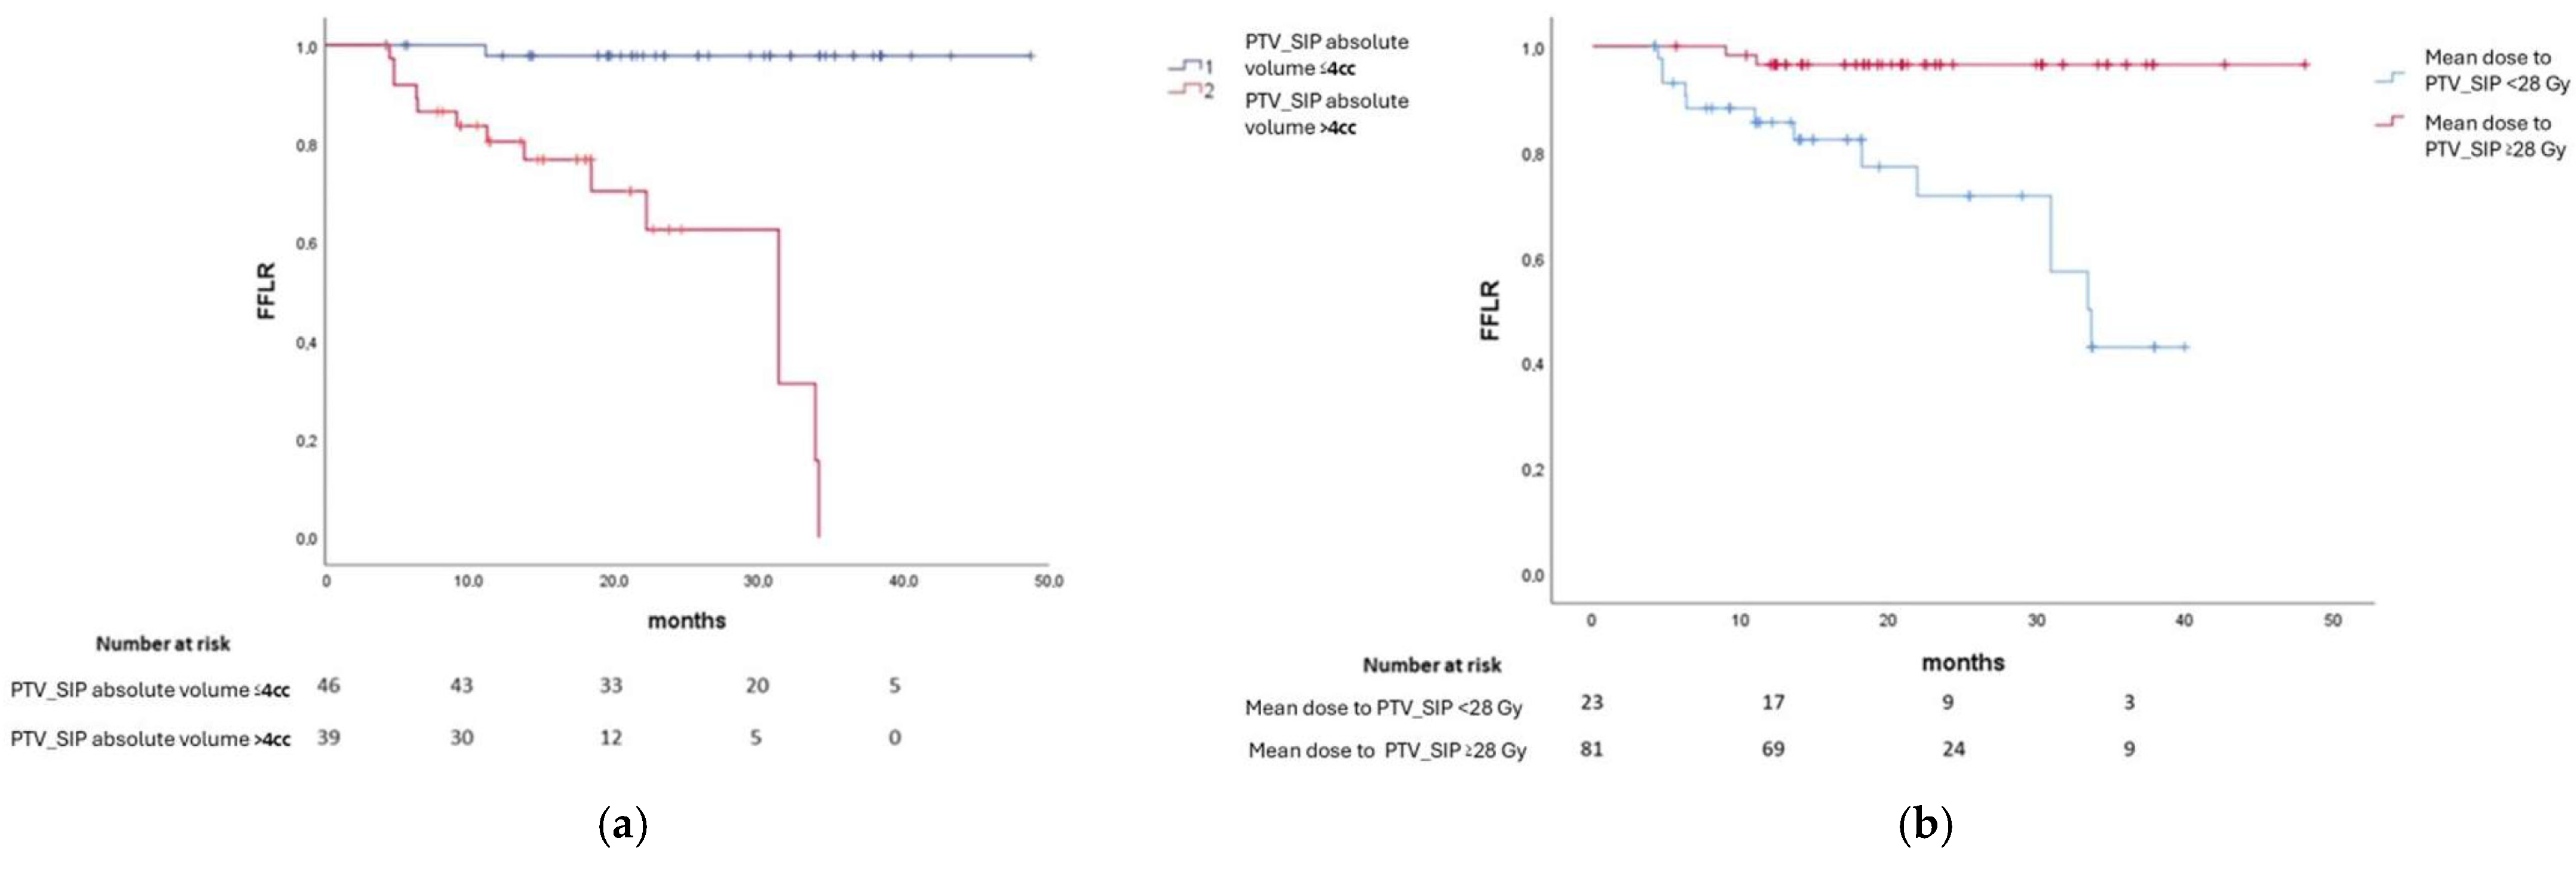

2.5.1. Primary Endpoint Analysis

3.2. Primary Endpoint